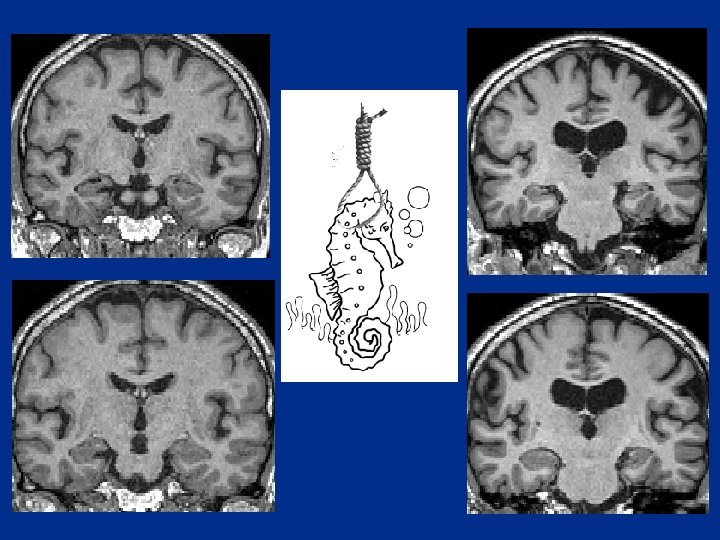

L’Atrophie hippocampique dans la MA v Précoce dans la maladie Sujet sain âgé Alzheimer Forme légère 25% d’atrophie Atrophie corrélée au MMS Alzheimer Forme modérée 40% d’atrophie

IRM dans la MA : Le cas idéal

• Atteinte Hippocampe G : Mémoire verbale épisodique (spécifiquement altérée/précoce dans la MA) • Hippocampe droit : Altération mémoire visuelle Associée parfois à une atrophie pariétale médiane

Grader l’atrophie?

Echelle de Scheltens 0 à 4

D: 0 G : 0

223 D : 2 -3+ G : 2

020133 DM D : 2+-3 - G : 3 -4

En cas de doute…. regarder sur les coupes antérieures

Comparer l’évolution H 59 ans. HDM : difficultés mnésiques. Tests : difficultés de calcul. Evolution : régression des troubles d’après le patient, confirmée par les tests 1997 2001 H 67 ans, droitier. 1997 : «un trouble de mémoire associé à l’âge » 2001 : Troubles mnésiques. Autonomie dans les activités vie quotidienne globalement préservée

1997 2001 Troubles de la mémoire Majoration des plaintes mnésiques Atrophie temporale interne+++ Evolution vers MA Atrophie hippocampique prédictive de l’évolution vers une MA Taux d’atrophie annuel (1, 5 %) + important pour MCI qui évolue vers MA (2%) LCR : prot tau et AB 42, précoces, avant MA PIB (marqueur de la plaque sénile) : 100% MA – 60% MCI – 30% sains…